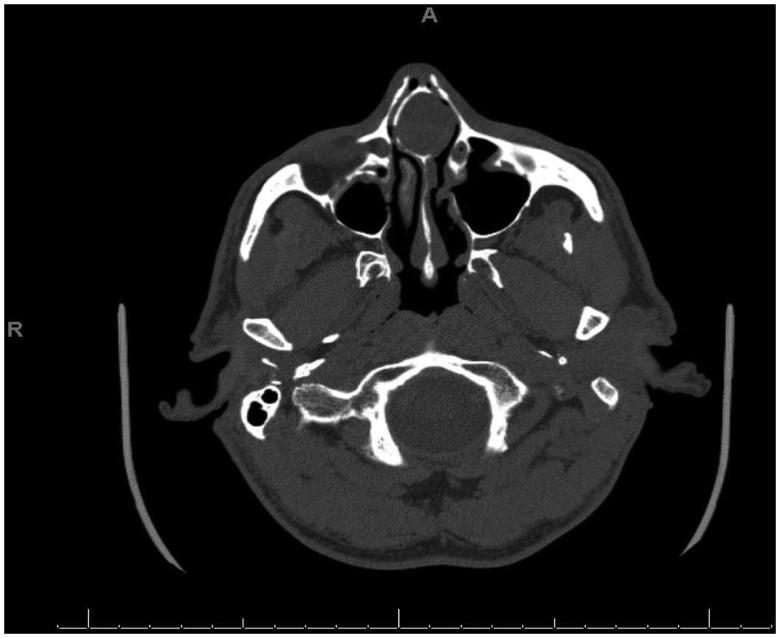

Paranasal sinus mucoceles are benign, expansive, cystic lesions which arise from retention of mucus secretions. They arise primarily in the setting of cystic degeneration of the sinus mucosa or secondarily in the setting of obstruction of the sinus ostium due to mucosal trauma or chronic inflammation. Septal mucoceles are rare. Only 10 cases to our knowledge have previously been reported. Patients are exclusively male, in their middle years, usually with a history of nasal trauma or nasal surgery. Nasal obstruction followed by headache present for 3 months to a year are the most common presenting symptoms. Here, we present a case of septal mucocele with dystrophic bone formation in a 57-year-old man arising 35 years after open septorhinoplasty treated successfully with total excision via an endoscopic, endoseptal approach. A review of the available literature was conducted to provide a consolidated update on diagnosis and management.

鼻窦黏液囊肿是一种良性、膨胀性、囊性病变,由黏液分泌物潴留引起。它们主要发生在鼻窦黏膜囊性退变的情况下,或继发于由于黏膜创伤或慢性炎症导致的鼻窦口阻塞。鼻中隔黏液囊肿罕见。据我们所知,此前仅报道过10例。患者均为中年男性,通常有鼻外伤或鼻手术史。鼻塞伴头痛3个月至1年是最常见的症状。在此,我们报告一例57岁男性鼻中隔黏液囊肿伴营养不良性骨形成的病例,该病例发生于开放性鼻中隔成形术35年后,通过内镜经鼻中隔入路成功进行了全切除。我们对现有文献进行了综述,以提供关于诊断和治疗的综合更新。